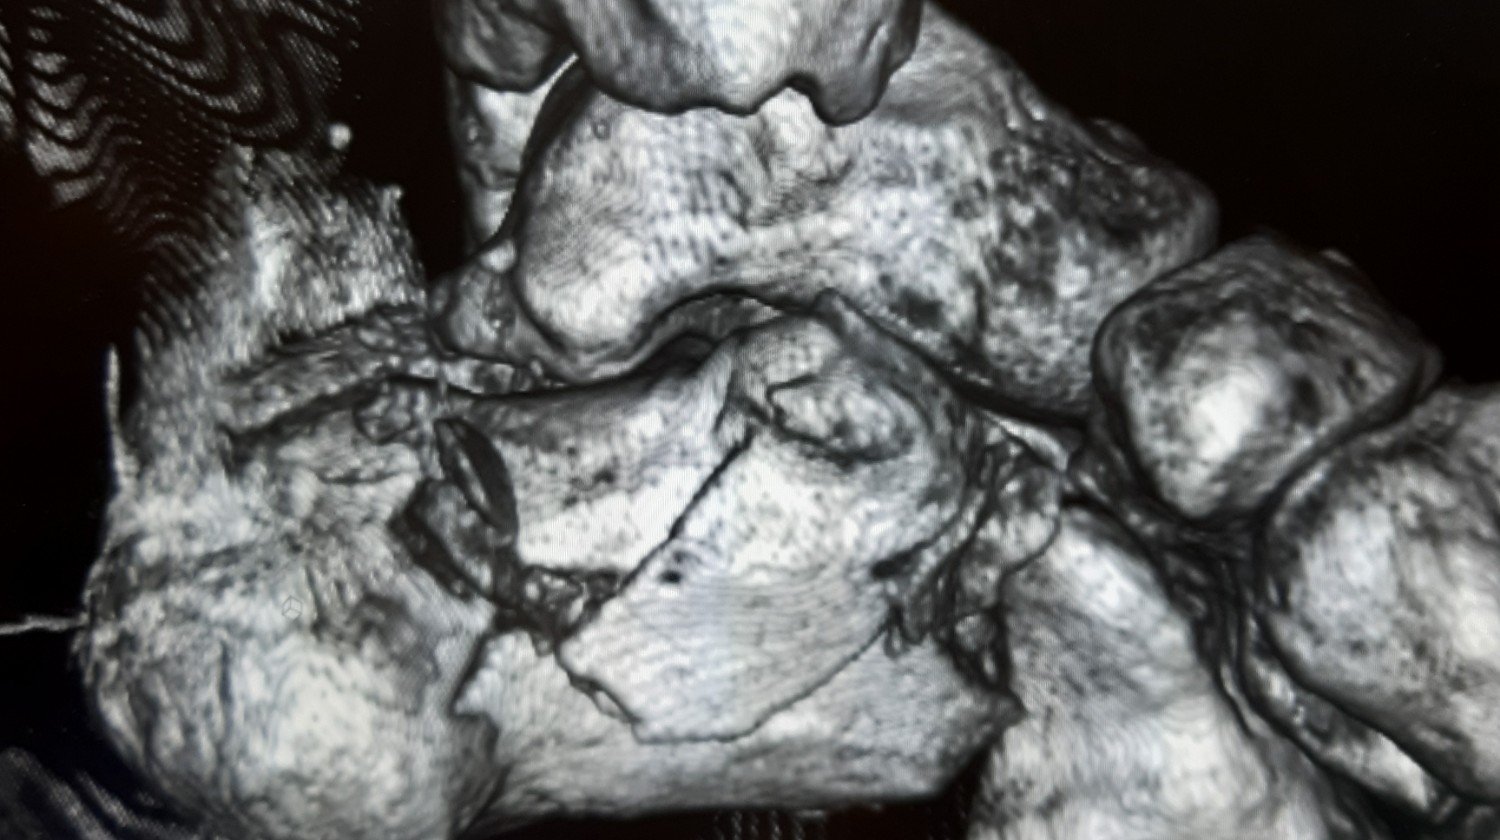

Po niedawnym wypadku moje życie zmieniło się drastycznie. Obrażenia uniemożliwiają mi normalne funkcjonowanie i powrót do zdrowia. Proszę o wsparcie finansowe na rehabilitację, która jest kluczowa dla mojego powrotu do sprawności. Każda wpłata będzie ogromną pomocą w mojej drodze do zdrowia. Dziękuję za każdą okazaną pomoc i wsparcie.